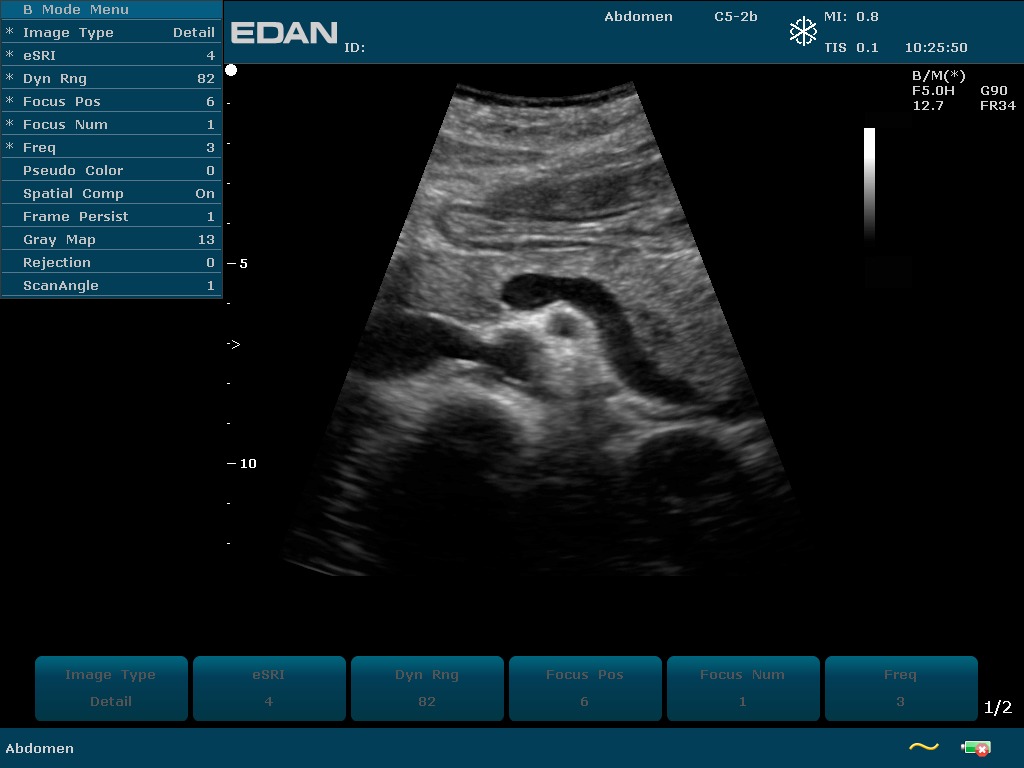

Прибор u2 143 фото